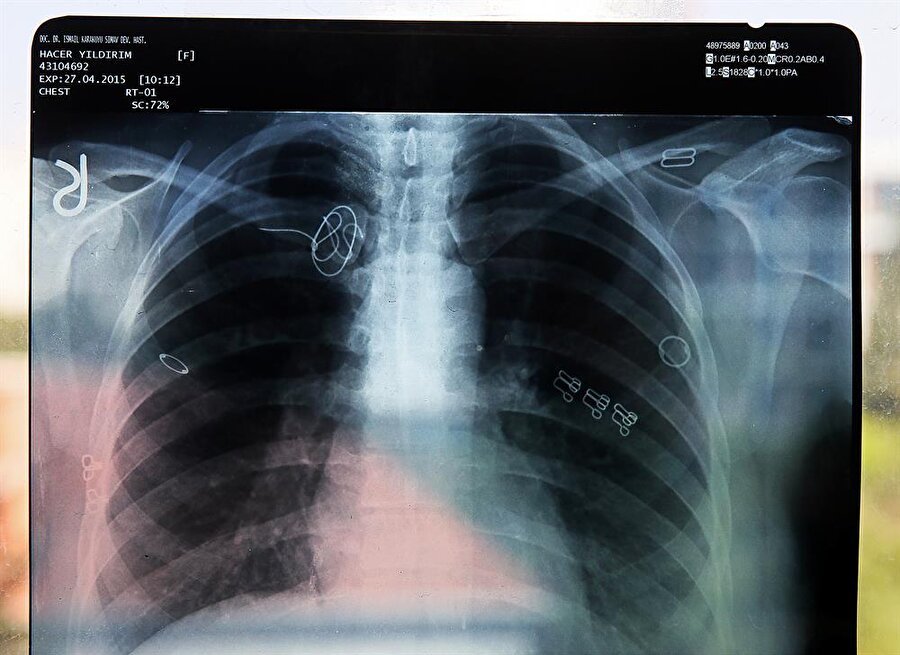

Kütahya'nın Simav ilçesinde yaşayan Hacer Yıldırım'a, 2015 yılında İzmir'de geçirdiği ameliyatın ardından artan ağrıları nedeniyle gittiği hastanede vücudunda kateter teli unutulduğu, telin yeni bir ameliyatla alınamayacağı ve ömür boyu bu şekilde yaşaması gerektiği söylendi.

Adli Tıp Kurumunca hazırlanan raporda, ameliyatın ardından davacının vücudunda kalan "CVP kateter kılavuz teli"nin ömür boyu kullanılacak kan sulandırıcı ilaçlarla hayati tehlike oluşturmayacağı belirtilerek, benzeri cihaz parçalarının yıllarca bu şekilde damarda kaldığı, bu tür durumlarda yeni bir cerrahi müdahalenin hastaya bırakılması gerektiği ifade edildi.